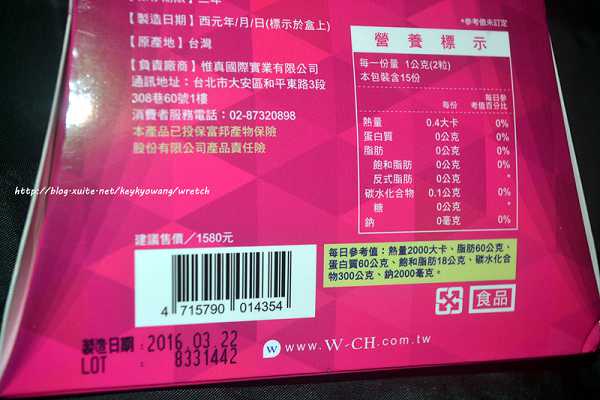

每一盒Supercut塑魔纖立塑膠囊都有三小包,每一小包有10顆膠囊

Supercut塑魔纖立塑膠囊的成分有:瓜拿那萃取粉、肉桂萃取粉、辣椒萃取物(唐辛子)、吡啶甲酸鉻、番瀉葉粉末、玉米澱粉、氧化鎂、二氧化矽。

食用方式:早晚餐前30分鐘各1粒,每日不超過2粒。(多食無益)

番瀉葉萃取物每日食用限量為12mg以下,